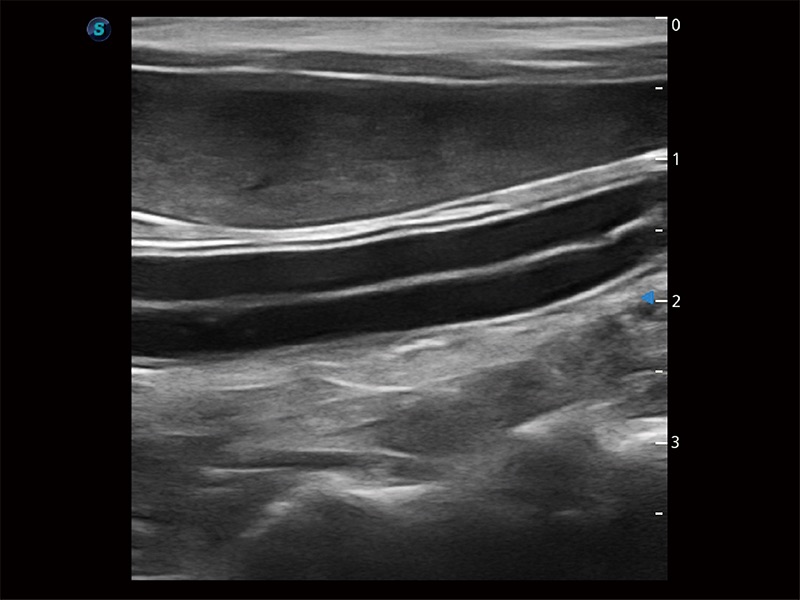

操作简便,无需高频度外力作用即可真实反映组织的形变,快速评估肿瘤良恶性。